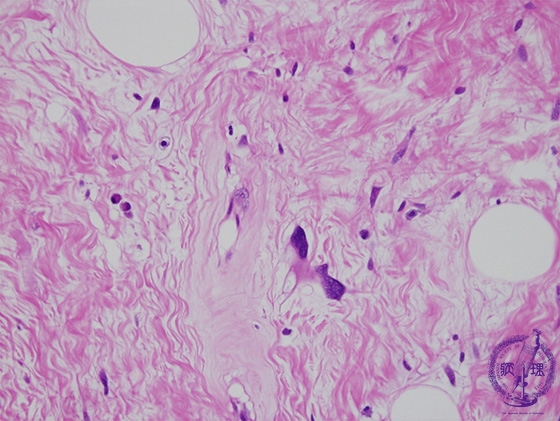

Microscopic findings (H.E. high power view): Hyperchromatic tumor cells with atypical nuclei scattered in the collagenous tissue.